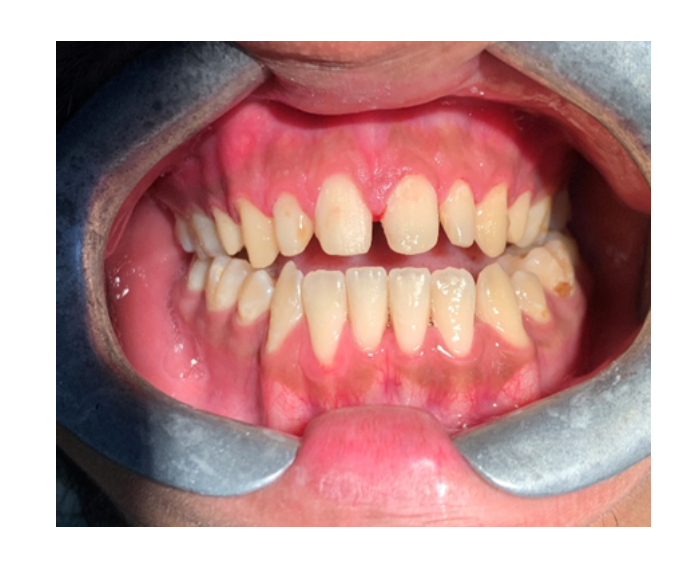

Clase I Protrusión

dental